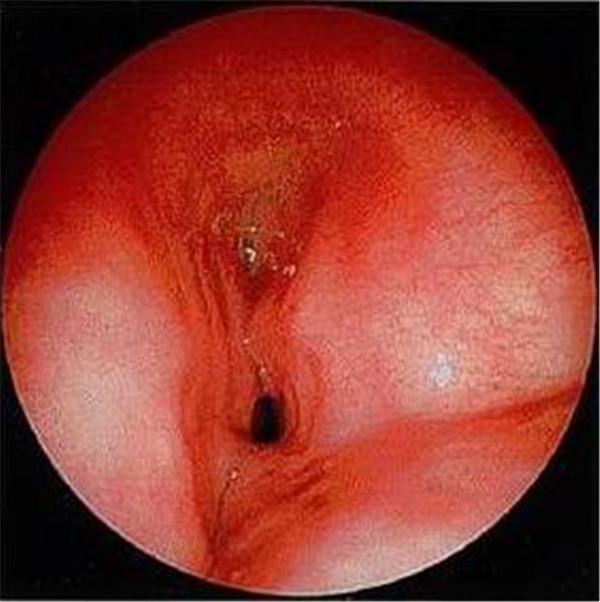

常见的镜下改变:

喉裂